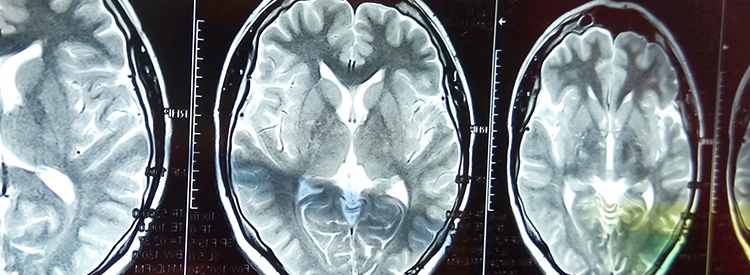

當大腦部分血流被切斷時,就會發(fā)生中風。當這種情況發(fā)生時,失去血液供應的腦組織就會受傷或死亡。根據(jù)大腦受損區(qū)域控制的功能,這會導致身體功能喪失。例如,如果控制左臂運動的區(qū)域受損,該臂就會變得虛弱或癱瘓。如果左臂控制感覺的區(qū)域也受到影響,手臂會麻木,或者也可能有燒灼感或疼痛感。由于大腦控制著我們所有的運動和感覺,包括視覺和言語,因此幾乎任何事物都可能受到中風的影響。

一般來說,中風有兩種類型:缺血性和出血性。缺血性中風是最常見的。當通向大腦部分的血管被堵塞時,通常會因血栓或類似于心臟病發(fā)作的膽固醇積聚而堵塞,就會發(fā)生缺血性中風。

出血性中風是較不常見的中風形式。當血管滲漏并且大腦內(nèi)部和周圍出血時就會發(fā)生這種情況。了解存在哪種類型的中風對于中風的早期治療至關重要。

中風治療進展緩慢。如果在最初幾分鐘內(nèi)進行治療,可以在急診室或醫(yī)院使用特殊藥物(阿替普酶或組織纖溶酶原激活劑)來逆轉(zhuǎn)或限制缺血性中風造成的損害。這種藥物可以分解阻塞血管的凝塊。如果在最初的幾分鐘到幾小時內(nèi)使用,可以避免或限制對大腦的任何損害。在使用阿替普酶之前,必須進行 CT 成像來確定中風類型,以確認中風不是出血性的。由于阿替普酶會分解血栓,因此如果用于出血性中風,可能會導致嚴重惡化或死亡。有時會治療出血性中風以避免進一步出血。